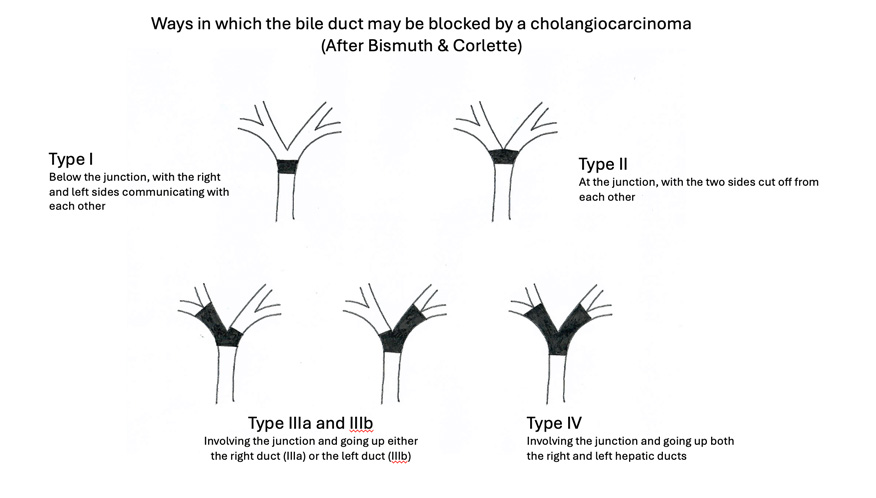

The type and extent of surgery depends on the location of the cancer within the liver or the biliary tract. The Bismuth classification (shown in the diagram above) is a practical and commonly used surgical classification of bile duct tumours at the junction of the right and left ducts. It is based on which ducts are involved and the extent to which they are involved. Cancers of the common bile duct (Bismuth Type I and II) require removal of the common bile duct and the regional lymph glands, with creation of a join between the right and left bile ducts on the one hand and the bowel on the other (so that bile can continue to flow into the bowel). The term used for this join is a Hepatico-jejunostomy. Tumours involving the confluence (Bismuth Type III) require, in addition, removal of a part of the liver. Type IV tumours – in the rare event of one being resectable - need an extended liver resection to achieve clear margins. Cholangiocarcinomas in the lower part of the bile duct, where it passes through the pancreas, should be managed with a pancreatoduodenectomy (also known as a Whipple operation).